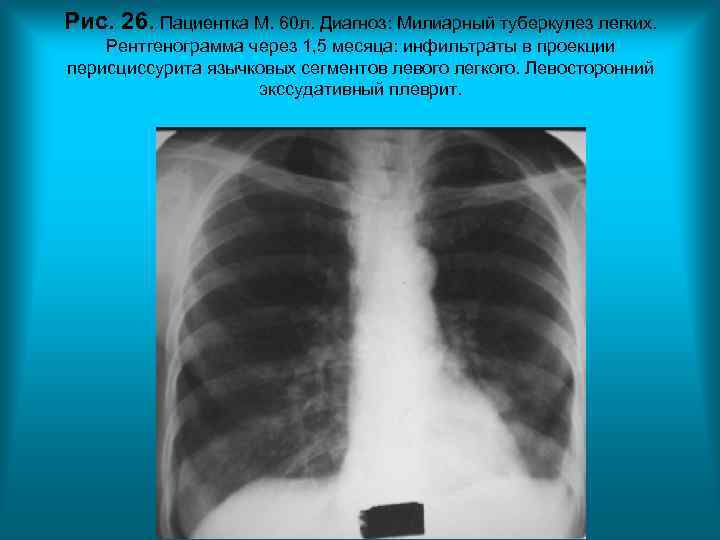

Рис. 26. Пациентка М. 60 л. Диагноз: Милиарный туберкулез легких. Рентгенограмма через 1, 5 месяца: инфильтраты в проекции перисциссурита язычковых сегментов левого легкого. Левосторонний экссудативный плеврит. Н. С. Воротынцева. С. С. Гольев Рентгенопульмонология